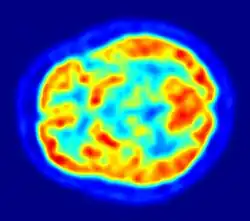

PET Imagem do encéfalo humano mostrando o consumo de energia.

De uma perspectiva biológica, a função do cérebro é gerar comportamentos que promovam a aptidão genética de um animal.[39] Para fazê-lo, ele extrai informações relevantes dos órgãos sensíveis para refinar as ações do animal. Sinais sensórios podem estimular respostas imediatas, como quando o sistema olfatório de um veado detecta o odor de um lobo; podem modular o padrão de atividade em andamento, como os efeitos dos ciclos de claridade-escuridão sobre o estado de sono-vigília de um organismo; ou suas informações podem ser armazenadas, para o caso de relevância futura. O cérebro gerencia sua complexa tarefa orquestrando subsistemas funcionais, que podem ser categorizados de várias formas: anatomicamente, quimicamente e funcionalmente.

Apesar do cérebro representar apenas 2% da massa corporal, ele é responsável por 20% de consumo total de oxigênio do corpo humano.[40]